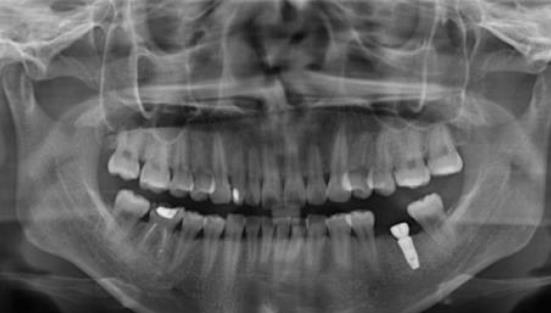

崔南醫(yī)生種植牙案例效果展示:

聽說重慶種植牙技術(shù)比較好,爸爸的牙齒少了很多,如果不及時(shí)的去補(bǔ)種就會(huì)影響到周圍的牙齒,假牙也不方便,所以決定去重慶口腔醫(yī)院種植牙齒,聽說種植牙齒跟真牙一樣,隨便用,不會(huì)對(duì)生活造成影響,經(jīng)過仔細(xì)了解重慶種植牙的價(jià)格后,決定帶爸爸去重慶牙衛(wèi)士口腔醫(yī)院看看。

種植牙前:

經(jīng)過多方面的對(duì)比之后決定帶爸爸去重慶牙衛(wèi)士口腔醫(yī)院種植牙,來到醫(yī)院后,醫(yī)生仔細(xì)地檢查了爸爸的身體,經(jīng)過仔細(xì)的確認(rèn)爸爸的身體沒有任何異常,醫(yī)生才選擇了手術(shù),手術(shù)前爸爸有些緊張,但醫(yī)生耐心的溝通,徹底消除了爸爸的緊張,開始準(zhǔn)備手術(shù),差不多花了3個(gè)多小時(shí),手術(shù)結(jié)束了。

種植牙中:

父親說,這次手術(shù)并沒有疼痛感,整個(gè)手術(shù)都很輕松,牙齒種植后也會(huì)有些不適應(yīng),可能是麻藥的緣故,醫(yī)生說麻藥藥效散去后會(huì)有一些疼痛感出現(xiàn),爸爸說是有一些疼痛感出現(xiàn),但不是很明顯,這種疼痛也可能是麻藥的緣故。

種植牙術(shù)后半年:

牙齒種植距今已有半年左右,爸爸說已經(jīng)適應(yīng)了這個(gè)情況,一切都很好,牙齒也可以咬上各種各樣的東西,現(xiàn)在爸爸再也不會(huì)擔(dān)心這種食物不能吃,那種食物不能吃,所有的東西都可以吃,硬的、酸的、甜的食物都不會(huì)造成牙痛,這回種牙齒真的很滿意。